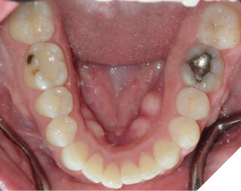

The majority of the orthodontic practices offer a period of “supervised retention” to their patients and communicates the customized retention recommendation with the patient’s general dentists. It is extremely important to work as a team to achieve long term clinical success in maintaining a functional bite and aesthetic smile. The general dentists continue to see their patients on a regular basis and have an opportunity to assess the orthodontic retainers and the bite after the supervised retention period is completed by the orthodontists. With great care, orthodontic retainers would serve for a long time (Fig. 1) without any major issues. However, in some cases, the failure to notice the clinical problems early on results in functional issues that would require a comprehensive orthodontic treatment to correct it (Fig. 2).

Fig. 2A

Fig. 2B

Fig. 2C